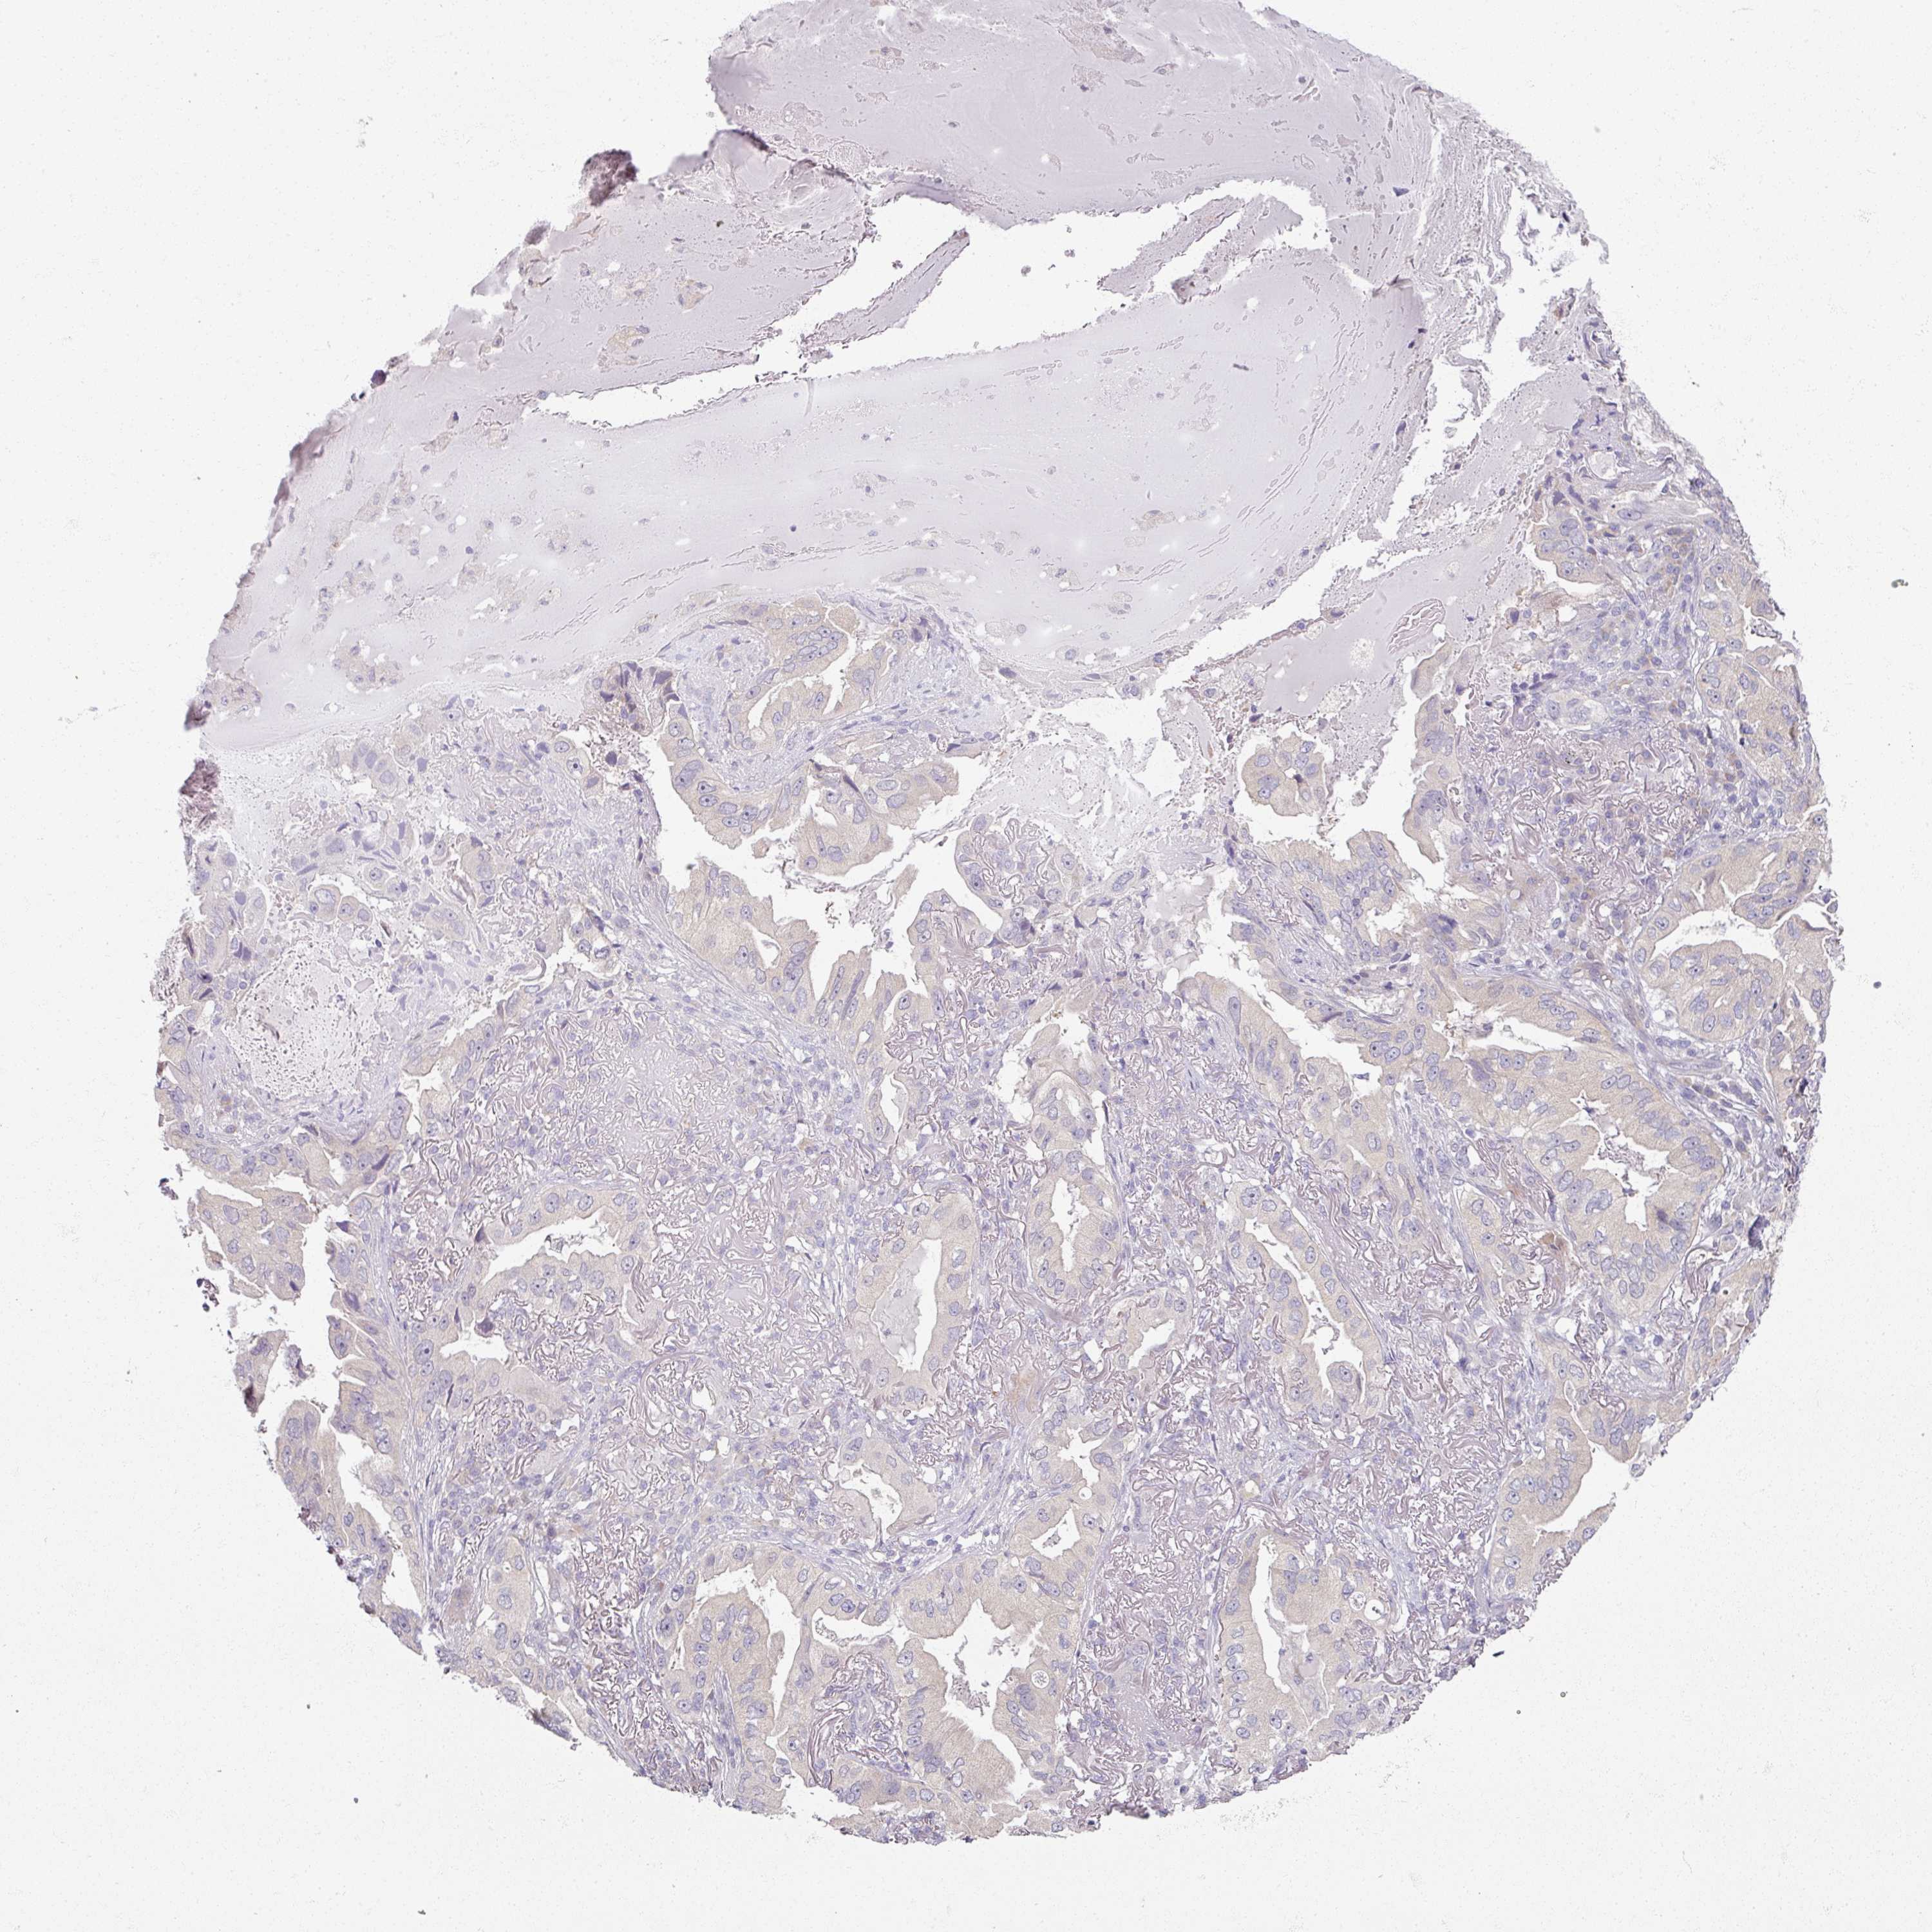

CANCER LUNG CANCER Show tissue menu

LUAD TCGA LUAD VALIDATION LUSC TCGA LUSC VALIDATION PROTEIN LUAD CPTAC PROTEIN LUSC CPTAC PROTEIN EXPRESSION